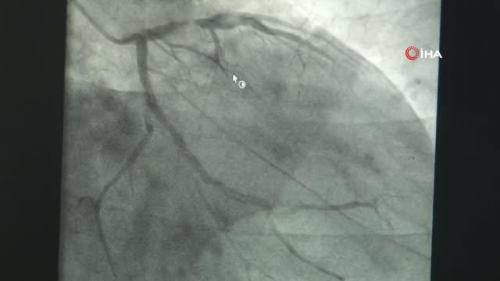

SAKARYA - 1970'li yıllardan beri uygulanan klasik ve güvenli bir tedavi yöntemi olan koroner bypass cerrahisi, gelişen teknolojiyle beraber daha az acı ve kesikle gelişmiş operasyon imkanı sunuyor. Klasik yöntemin yanı sıra hastaya ameliyat sonrasında daha fazla konfor sağlayabilen minimal invaziv bypass yöntemi hakkında Kalp Damar Cerrahi Op. Dr. Murat Güçlü Elevli bilgilendirdi. İnsanlarda en sık görülen sağlık sorunların başında gelen koroner arter hastalığı 1970'li yıllardan beri klasik ve güvenli bir yöntem olarak görülen koroner bypass cerrahisi ile tedavi ediliyor. Teknolojinin gelişmesiyle ivme kazanan sağlık sektöründe de yeni tedavi yöntemleri geliştiriliyor. Teknolojinin katkılarıyla klasikleşmiş olan ameliyatların yerine; daha az kesilerle, hastaların canını daha az yakacak lokal bölgelere müdahaleler yapılıyor. Bu çerçevede göğüs kemiği kesilmeden bypass olanağı ise daha az kesi ile minimal invaziv yöntemi ile gerçekleştiriliyor. Özel Adatıp Hastanesi Kalp Damar Cerrahi Op. Dr. Murat Güçlü Elevli, 1980'li yıllarda Amerika'da ortaya çıktıktan sonra uzun bir süre popülerliğini yitiren ve daha az kesi ile yapılan mimimal invaziv koroner bypass ameliyatının uzun yıllar sonra tekrardan gündeme geldiğini söyledi. Bu konuda öncülerden biri olan Ukraynalı cerrah Prof. Dr. Oleksandr Babliak'ın kliniğine giderek tekniği öğrendiğini aktaran Elevli, bu ameliyatın her hastaya yapılmadığını, tetkikler neticesinde uygun görülen hastalarda yapıldığını aktardı. "Teknolojinin katkılarıyla bazı müdahale olanaklarımız ortaya çıkmaya başladı" Teknolojinin gelişmesiyle birlikte sektörün de geliştiğini belirten Özel Adatıp Hastanesi Kalp Damar Cerrahi Op. Dr. Murat Güçlü Elevli, "Koroner arter hastalıkları en sık görülen sağlık sorunlarından bir tanesi. Bu hastalıkların tedavisinde de koroner bypass cerrahisi 70'li yıllardan beri uygulanan klasik ve gayet güvenli bir tedavi yöntemi. Fakat tabi her şey durduğu yerde durmuyor, teknoloji ilerliyor. Bu ilerlemeyle birlikte sağlık hizmetlerinde de koroner bypass cerrahisinde de yeni gelişmeler var. Teknolojinin katkılarıyla artık klasikleşmiş olan ameliyatların yerini daha az kesilerle, hastanın canını daha az yakacak şekilde bazı müdahale olanaklarımız ortaya çıkmaya başladı. Diğer yöntemde olduğu gibi buda açık kalp ameliyatı şeklinde geçiyor. Kalp-akciğer makinesine bağlanarak yapılan bütün ameliyatlar açık kalp ameliyatıdır. Dolayısı ile kesi yandan veya önden olmuş bu açık kalp ameliyatı terimini değiştirmiyor. Fakat göğüs kemiğinin kesilmemiş olmasından dolayı, göğüs kafesinin körük mekanizması çokta fazla bozulmamış oluyor ve böylelikle hastaların ameliyattan sonraki dönemdeki konforları çok daha fazla oluyor" dedi. "Kontrollü olmak ve bilimsel verileri takip etmek lazım" Minival İnvaziv bypass cerrahisi hakkında açıklamalarda bulunan Elevli, "Bütün hastalara bu şekilde yaklaşmak çok doğru olmayabilir. Bu teknikler henüz daha yeni ve bunların uzun dönem sonuçları ile ilgili elimizde çokta fazla bir yayın yok. Ama tabi yayın yok diye yapmayalım da olmaz. Dolayısı ile kontrollü bir şekilde daha seçilmiş ve uygun gördüğümüz hastalardan başlayarak bu yöntemi kullanmayı tercih edebiliyoruz. Bizim elimizde bir altın standart yani klasik koroner bypass ameliyatı var. Türkiye'de senede 15 bin civarında hastaya uygulanan ve gayet başarılı sonuçları olan, yüzde 1'in altında ölüm oranları olan, sakatlanma oranları çok düşük olan bir cerrahi yöntem. Bu bizim altın standartımız. Amacımız; küçük kesiyle bypasslarda da aynı kalite ve başarıyı yakalayabilmek. Bunu yaparken biraz temkinli davranıp git gide daha çok hastaya bunu uygulama yolunda gidiyoruz. Ama tabi hep kontrollü olmak ve bilimsel verileri takip etmek lazım" diye konuştu. "Bu yöntemi tetkik ettik ve öğrendik" Uzun yıllar pek fazla popüler olmayan fakat son yıllarda yeniden gündeme gelen yöntemi yerinde öğrendiğini belirten Elevli, "80'li yıllarda aslında ilk Amerika'da ortaya çıkmış olan bu küçük kesiyle bypass yöntemleri bir ara pek fazla yapılmaz hale geldi. Son zamanlarda özellikle Ukrayna Kiev'den ünlü bir cerrah hocamız var; Prof. Dr. Oleksandr Babliak. Onun popülarize ettiği bir yöntem olarak tekrardan ortaya çıktı. Biz de bu bağlamda Ekim ayında, kendisinin Kiev'deki kliniğine konuk olduk. Orada bu yöntemi tetkik ettik ve öğrendik. Döndükten sonra da uygun hastalarımızda bu yöntemi uygulamaya başladık Adatıp Hastanemizde" şeklinde konuştu. "Daha rahat bir yaşam konforu ameliyattan hemen sonra elde edilebiliyor" Yapılan ameliyatın avantajlarından söz eden Elevli, "Klasik bypass ameliyatlarında göğüs kemiği kesilerek ameliyat yapılıyor. Bu da yaklaşık 20-25 santimetrelik bir kemik kırığı anlamına geliyor. Bunun kaynaması da yaklaşık 6 ila 8 haftalık bir süre alıyor. Bu durumda hastanın ameliyattan sonra sağa sola dönme hareketlerinde kısıtlama olabiliyor. Bu da hastanın ameliyat sonrası yaşam konforunu oldukça kısıtlayan, azaltan bir şey. Küçük kesiyle bypass ameliyatları, kaburga arasından ufak bir kesiyle yapıldığı ve göğüs kemiğinin de bütünlüğü bozulmadığı için hem göğüs kafesinin körük mekanizması bozulmamış oluyor böylelikle hastanın nefes alıp vermesinde bazı zorluklar yaşıyorduk bu biraz daha azalmış oluyor hem de hasta istediği gibi sağına soluna dönebiliyor. Daha rahat bir yaşam konforu ameliyattan hemen sonra elde edilebiliyor. Bu da hastanın daha çabuk bir şekilde normal hayatına dönmesine katkıda bulunuyor" ifadelerini kullandı.